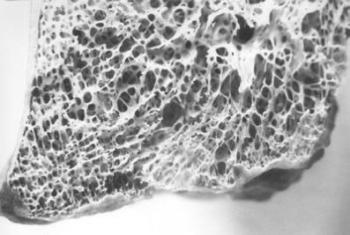

14. ábra. A vese glomerulusai, a kanyarulatos csatornák alapi hártyája, valamint a csatornákban lévő cilinderek jól festődnek PAS festéssel. 71 éves férfi mumifikálódott veséje, 100× nagyítás